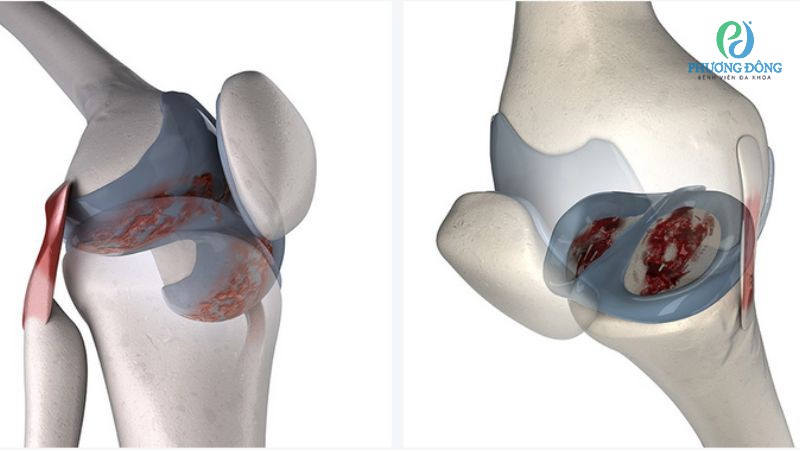

Chấn thương sụn chêm đầu gối

Rách sụn chêm có thể xuất hiện riêng lẻ nhưng đa phần thường đi kèm với đứt dây chằng chéo. Đôi khi đây cũng có thể là hệ quả của đứt dây chằng chéo không được can thiệp kịp thời và đúng cách.

Vùng tổn thương sụn chêm nhỏ, ở vùng giàu mạch nuôi có thể tự liền lại sau 6 tuần, nếu tiếp nhận điều trị và chăm sóc đúng cách. Ngược lại với những vết rách lớn, phức tạp hoặc rách ở vị trí khó liền, người bệnh cần can thiệp phẫu thuật nội soi để bảo tồn cấu trúc giải phẫu.

Đối với trường hợp hy hữu, sụn chêm không thể khâu sẽ tiến hành cắt một phần hoặc hoàn toàn nhằm hạn chế cơn đau và phục hồi vận động khớp đối. Tuy nhiên phương án này về lâu dài sẽ tác động nhất định đến tốc độ thoái hóa, do khớp gối bị mất sụn chêm.